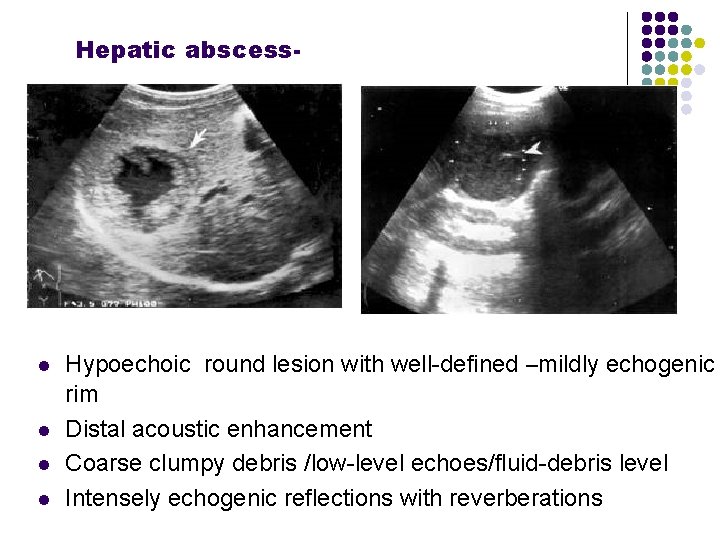

Hepatic abscess- l l Hypoechoic round lesion with well-defined –mildly echogenic rim Distal acoustic enhancement Coarse clumpy debris /low-level echoes/fluid-debris level Intensely echogenic reflections with reverberations

l l Hypoechoic round lesion with well-defined –mildly echogenic rim Distal acoustic enhancement Coarse clumpy debris /low-level echoes/fluid-debris level Intensely echogenic reflections with reverberations